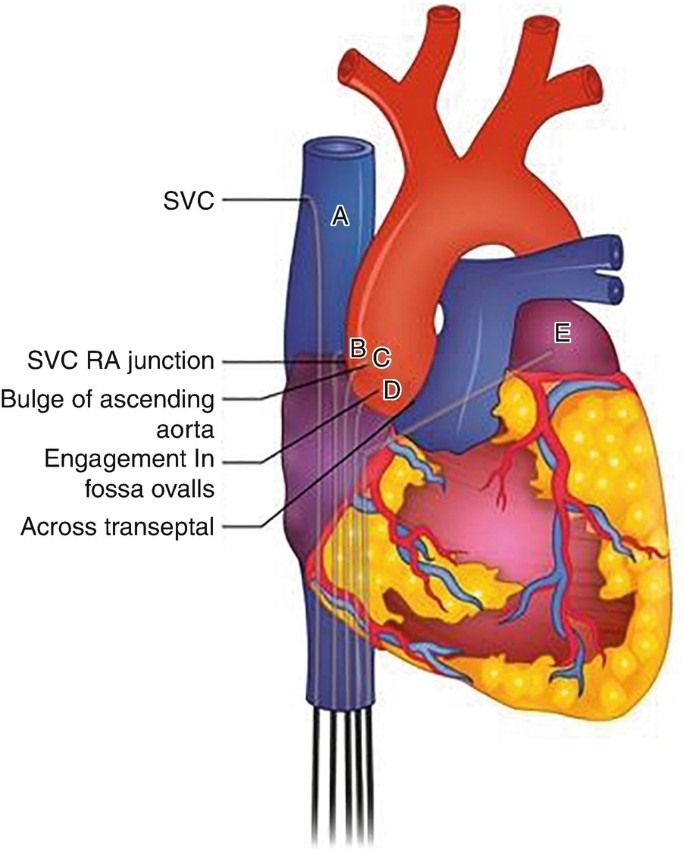

Overview

Package includes:

Days in hospital : 2 to 3 Days (For patient and one attendant)

Days in hotel : 3 Days (For patient and one attendant)

Room type in hospital : Shared

Room type in hotel : Private

Hotel category: Standard

Value added benefits of the Balloon Mitral Valvuloplasty:

Ø Doctor consultation charges

Ø Lab tests and diagnostic charges

Ø Room charges inside hospital during the procedure

Ø Surgeon Fee

Ø Nursing charges

Ø Hospital surgery suite charges

Ø Anesthesia charges

Ø Routine medicines and routine consumables (bandages, dressings etc.)

Ø Food and Beverages inside hospital stay for patient and one attendant.

Extra benefits:

ü Interpreter

ü Visa assistance

Ø Site tourism of the city

Ø Follow up with the doctor

Ø Airport pick up and drop

Ø Free online consultation with the doctor

Ø Priority appointments with the doctor

Ø Room upgrade from sharing to private